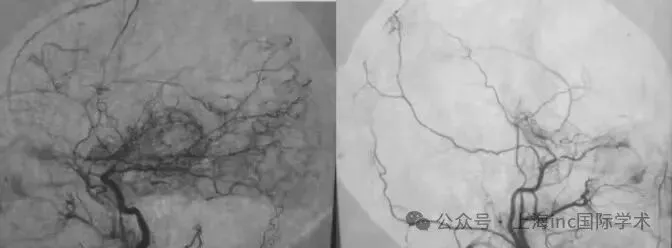

出血型烟雾病再出血率高、预后差,一旦发生,极易导致残疾甚至死亡。可同样罹患出血型烟雾病,有人能多年平稳无恙,有人却反复出血,风险天差地别。 有没有办法预测谁会再次出血?手...

烟雾病是一种罕见的脑血管闭塞病,成人患者常以脑出血发病,再出血风险高、预后差。血管搭桥手术是主要治疗手段,但颞浅动脉大脑中动脉双旁路术到能否有效预防下一次灾难性的出血呢?...

在神经外科领域,烟雾病一直是个棘手难题。患者大脑主要血管逐渐闭塞,代偿形成脆弱异常的烟雾状血管网,不仅容易导致脑缺血,更可能在搭桥手术后出现致命的出血性脑高灌注综合征(...